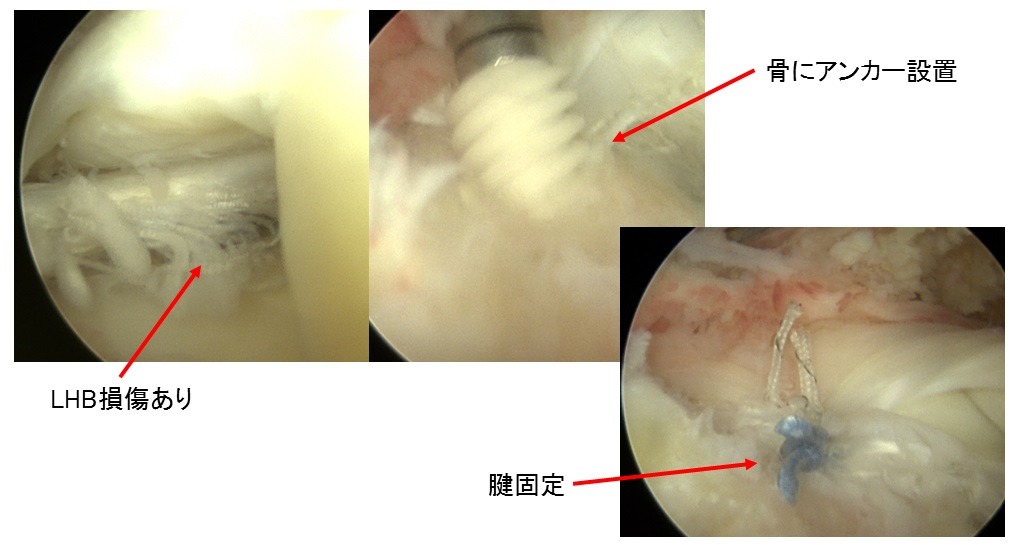

⑤上腕二頭筋長頭筋腱(LHB)の腱固定

- 上腕二頭筋腱長頭(LHB)固定もしくは切除:必要に応じてLHBの処置を行います。

- 肩峰下除圧:腱板の上の骨を削って腱板の通り道をつくります。

- 腱板縫合:Suture-bridge法といいます。

③腱板縫合

上腕骨頭(大結節Footprint)が露出してしまっている。